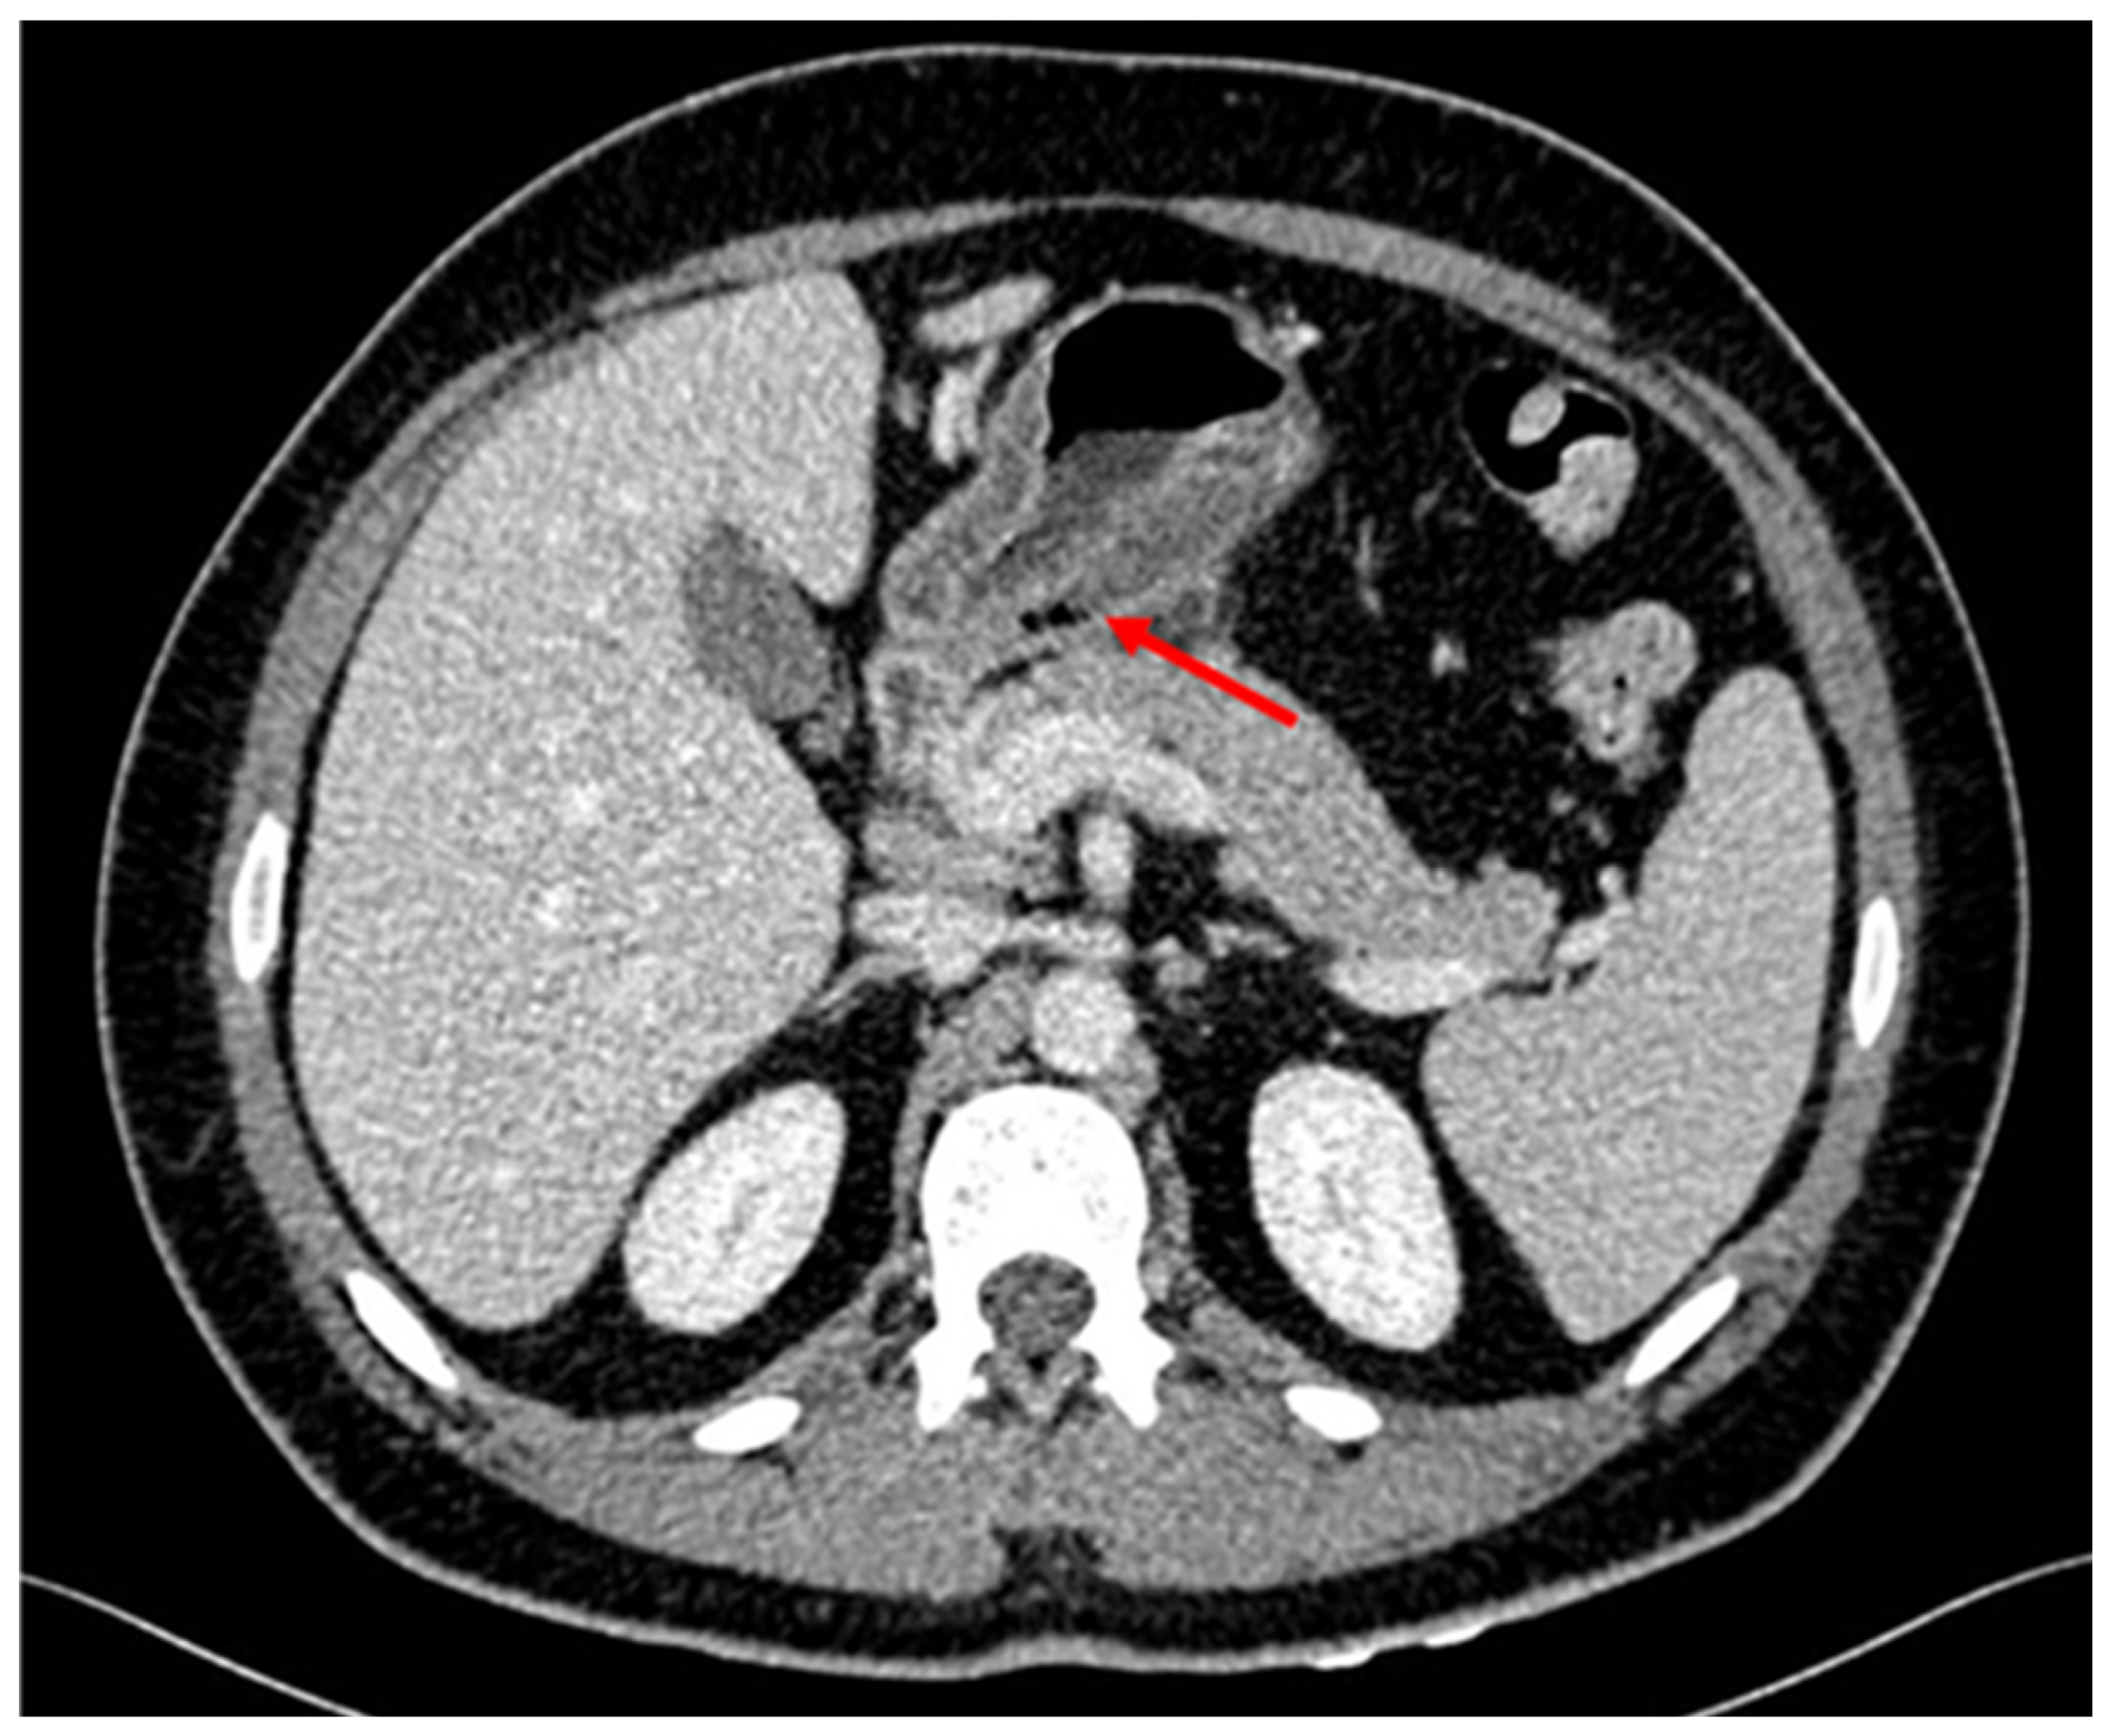

Patient was hospitalized in the Gastroenterology ward with suspicion of malignancy after evaluating endoscopy features. For extension screening a CT scan was performed showing wall thickening of the gastric antrum with intramural gas bubbles. Intramural gas could be possibly related to ulceration or to the previous biopsies. There was slight fat stranding as well as some sub centimeter and non-specific lymph nodes. No signs of distal spreading were seen on the thorax or rest of the abdomen. Tumor markers were negative.

Figure 2. Thickening of the wall of the gastric antrum showing some atypical gas bubles.